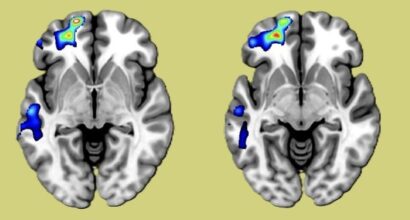

The VAMI-project, led by Professors Jarmo Hietala and Raimo K. R. Salokangas, focuses on the etiology and treatment of psychotic disorders through an integrative research approach. It combines clinical research with neuroimaging, genetics, metabolomics, immunological, and microbiomics to uncover etiological mechanisms underlying psychosis. Etiology is in the very center for developing treatments that truly improve the prognosis of patients with psychotic disorders (see Figure).

- Neuroimaging: PET and MRI techniques to study brain function and neurotransmitter systems as well as brain morphology.